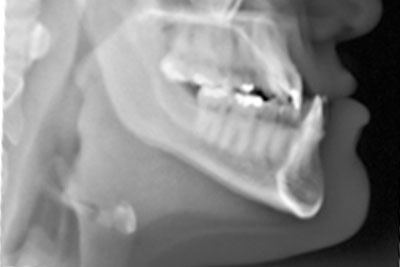

The upper jaw (maxilla) consists of two bones that fuse together during adolescence. In young children, these bones are still connected by a flexible suture in the middle of the palate. A palatal expander applies gentle outward pressure on this suture, gradually widening the jaw.

Initial Consultation: We examine the child’s bite, take x-rays, photos, and digital scans.